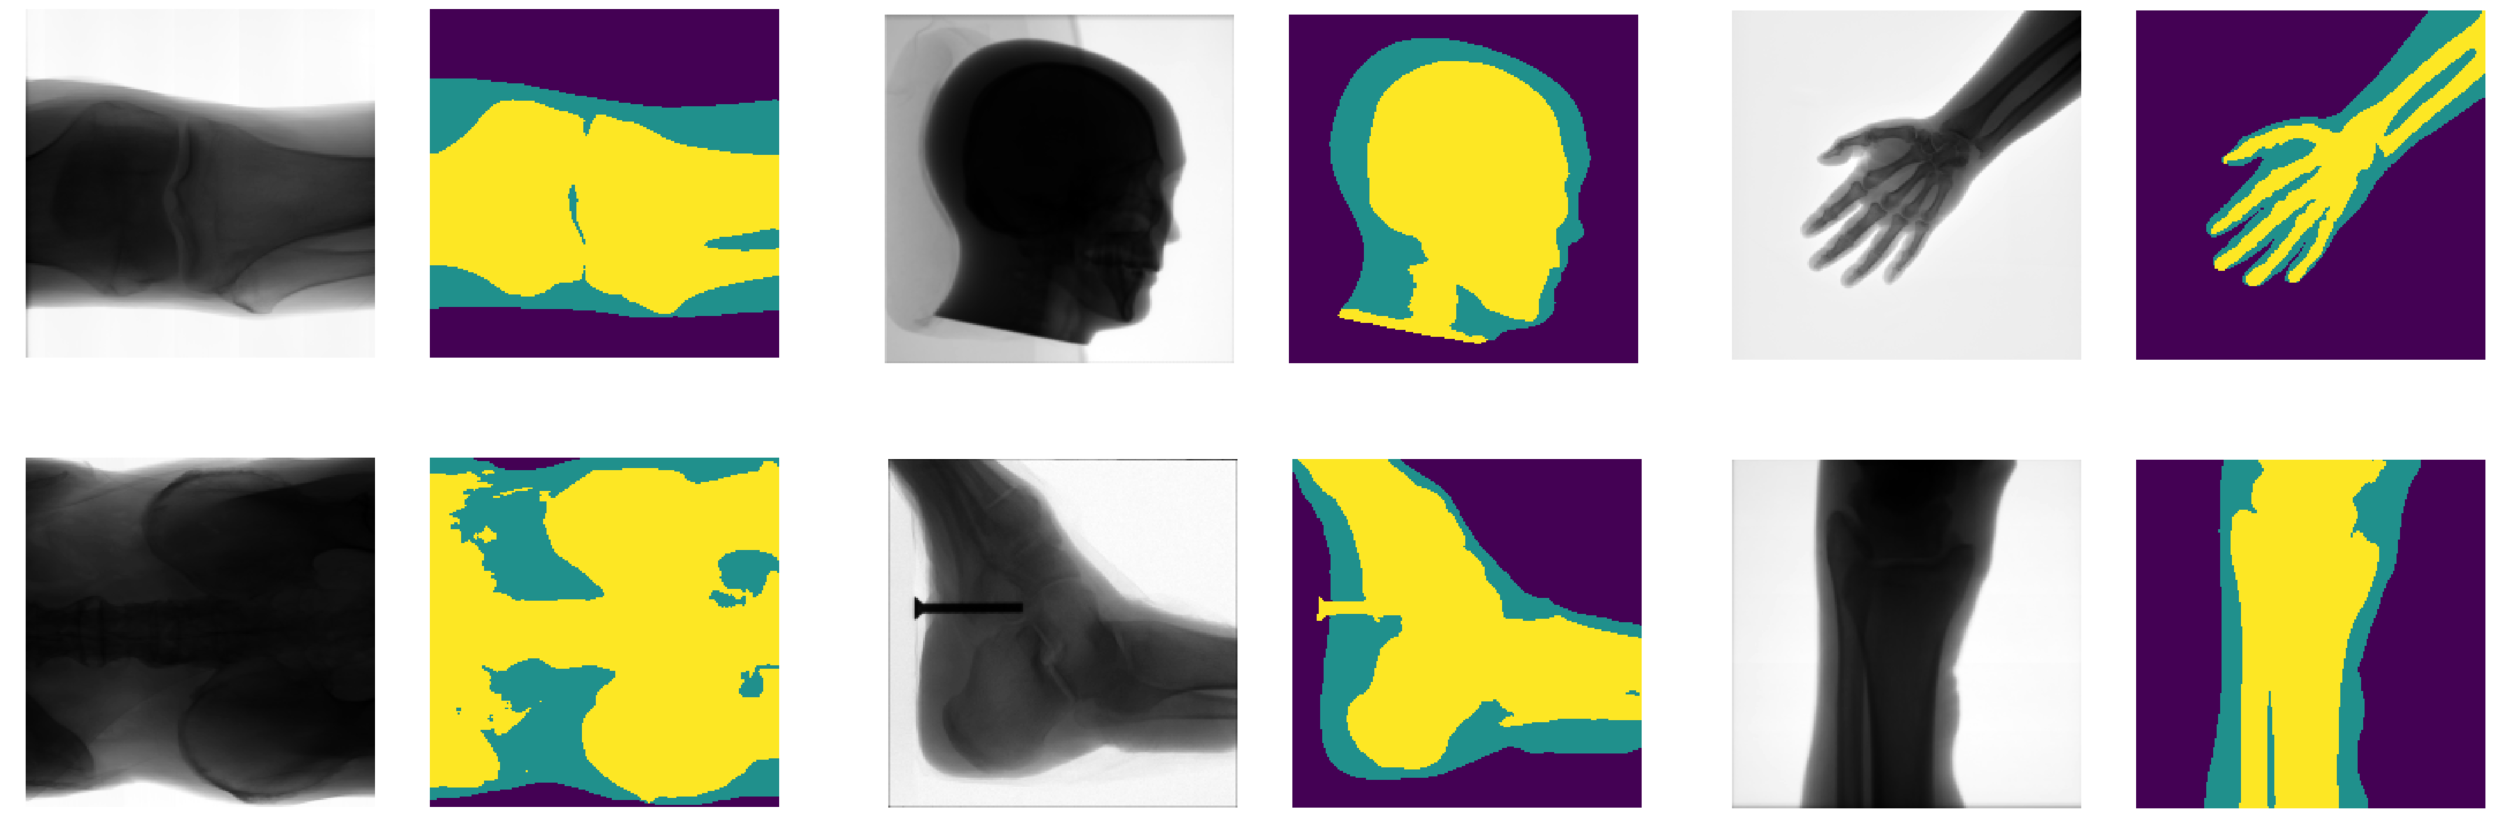

SegNet

- The network has more than 15 Million free parameters.

- To find the values of the parameters that produce the correct segmentation, it has been trained on 1.3 Million images.

XNet

-

Original Architecture based on SegNet but fewer parameters.

- Trained on 150 images, artificially augmented to more than 7000.

Results

- Generalises well even for unseen categories!

- Overall accuracy on test set: 92%

- Soft tissue TP/FP rate: 82% / 4%